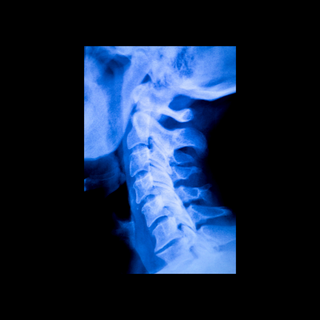

From cervical spine syndromes to lumbar herniations causing lumbalgia, our spine specialists conduct comprehensive evaluations and offer treatment options, including conservative therapies, minimally invasive procedures, and spinal surgery when necessary.